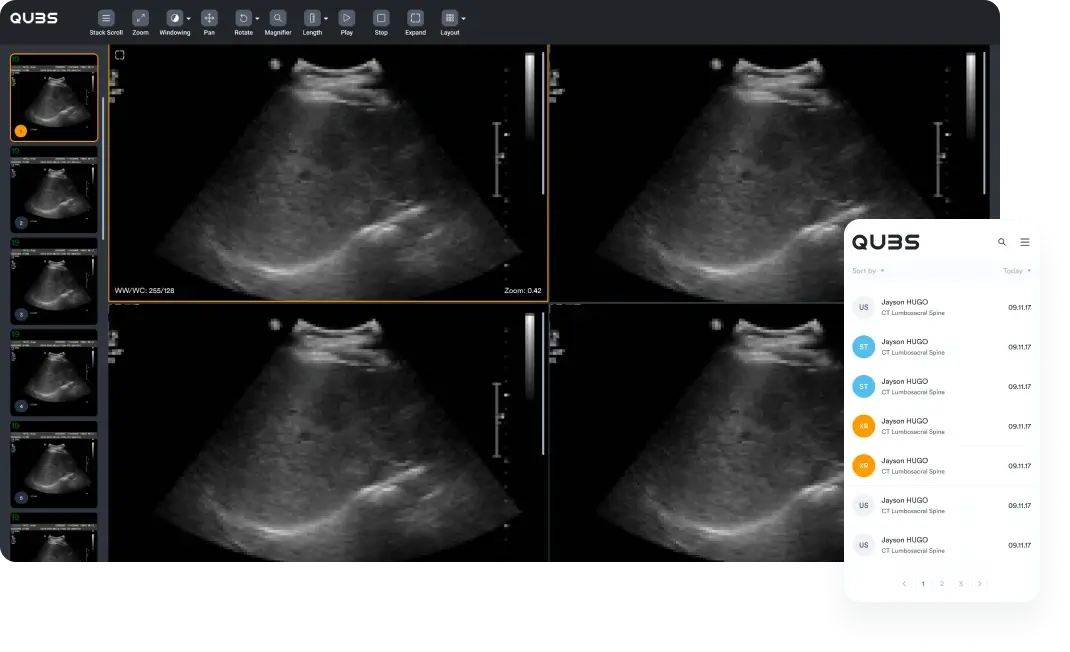

With QUBS' cloud-based RIS/PACS system, immediate access to your patients' images and reports is at your fingertips. Designed for mobile ultrasound and x-ray clinics, our platform ensures data security, accessibility, and efficiency, all at a reduced cost. Your essential data is always secure and just a click away, streamlining your clinic's operations.